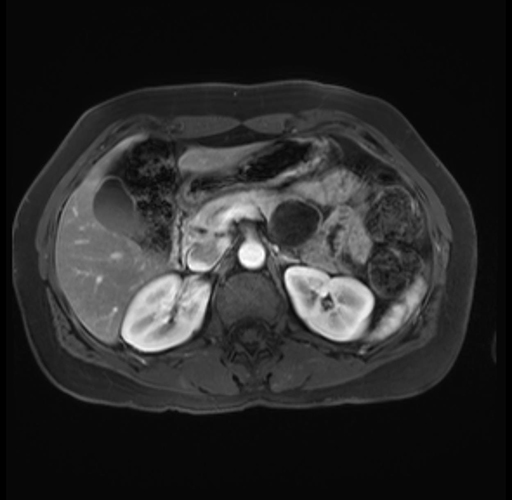

Imaging Analysis

Look through the patient's CT scan to identify any areas of concern for the necessary procedure.

Based on your CT findings, which issue(s) are present and would give reason for "planned slowing down moment(s)" in this case?